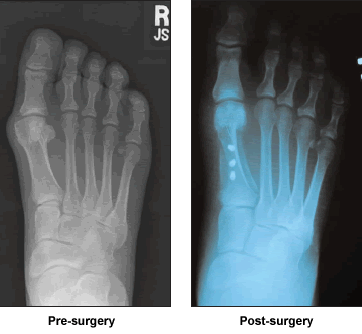

My daughter had moved to San Francisco, but my pain became unbearable. In August of 2004, I searched for information about my problem on The Baptist's web site. There I found Dr. Leavitt's credentials and read his articles on foot reconstruction. I telephoned The Baptist and asked to speak to Dr. Ken Leavitt. At his request, I had x-rays sent to him, then I talked to him twice more by phone from my home in Santos, Brazil.

I owe Dr. Leavitt so much that sometimes, I look at my feet to make sure all has been real. Thank God. Thank you Dr. Leavitt a million times. My feet now make me happy. They are doing very well. They are the feet I had dreamed of for a lifetime. They still complain when in pointed shoes. It will be for a while, it seems to me. I keep exercising and stretching the tissues. It has been three months now and I am running easily and comfortably along the hot sands of my country.